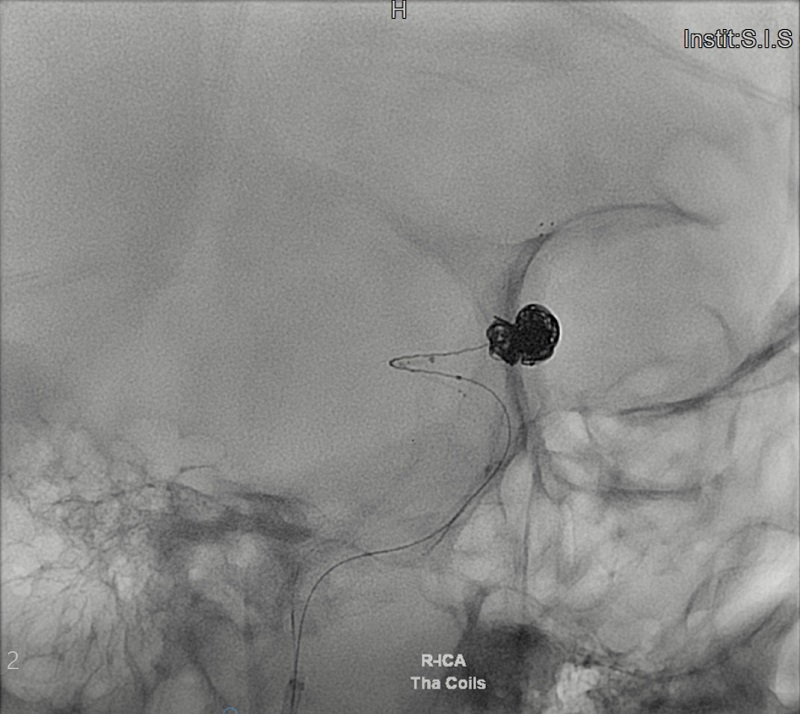

Hình ảnh MRI cho thấy túi phình mạch máu bị vỡ của bệnh nhân T.V.H khá lớn và ở vị trí nguy hiểm. Ảnh: BVCC Khi vào đến khoa cấp cứu, các bác sĩ tại bệnh viện Đa khoa Quốc tế S.I.S Cần Thơ nhanh chóng tiếp nhận và tiến hành đo huyết áp, cho bệnh nhân thở oxy và chụp MRI để xác định nguyên nhân gây đột quỵ và hôn mê. Sau khoảng 10 phút chụp MRI mạch máu não các bác sĩ đã phát hiện ngay bệnh nhân đã bị vỡ túi phình mạch máu não vị trí động mạch thông trước rất phức tạp… TS.BS Trần Chí Cường – Giám đốc bệnh viện trực tiếp thực hiện ca can thiệp cho biết: “Đây là trường hợp rất hi hữu được cứu sống. Vì bệnh nhân H. xuất hiện triệu chứng đau đầu đột ngột dữ dội, co giật, hôn mê sau đó lại tỉnh dậy và lặp lại 3 lần như vậy… Khả năng mỗi lần bệnh nhân lên cơn co giật hôn mê là rơi vào tình trạng đợt xuất huyết não từ túi phình vỡ ra. Thông thường, các trường hợp bệnh nhân xuất huyết do vỡ túi phình nguy cơ tử vong do vỡ lần đầu là khoảng 30-50% tùy theo lượng máu chảy, lần 2-3 nguy cơ tử vong tăng lên 80-90%”. Bệnh nhân H. đã được can thiệp đặt coil thành công. Ảnh: BVCC Phương pháp điều trị phình mạch máu não vỡ bao gồm phẫu thuật kẹp túi phình và can thiệp nội mạch DSA đặt coils. Theo nhiều nghiên cứu trên thế giới can thiệp nội mạch DSA thì an toàn hơn và ít xâm lấn. “Với can thiệp nội mạch DSA có thể đặt coils đơn thuần khi túi phình cổ hẹp, khi túi phình cổ rộng đang xuất huyết như bệnh nhân H. kỹ thuật can thiệp vô cùng khó khăn vì phải dùng stent che cổ túi rồi sau đó mới đặt coil được. Tuy nhiên vấn đề là nguy cơ tắc stent cấp vì bệnh nhân không thể uống thuốc chống tắc stent trong lúc này” – BS Cường giải thích. “Với những khó khăn như thế, ekip chúng tôi đã dùng kỹ thuật tạo hình cổ túi phình lúc đặt coils bằng stent lấy huyết khối, khi đặt coils xong cầm máu được chúng tôi tiến hành kéo stent ra và bệnh nhân không cần dùng thuốc chống đông sau đó” – BS.CK2 Ngô Minh Tuấn người cùng thực hiện thủ thuật chia sẻ thêm. Chị Thủy tâm sự: “Khi bác sĩ ra ngoài báo can thiệp thành công tôi vô cùng vui mừng. Tôi nghĩ chồng tôi được phù hộ và có một phép màu nào đó chứ không là không thể qua được. Bác sĩ Cường rất nhiệt tình, giản dị, thân thuộc như người trong gia đình vậy. Do đó, tôi vô cùng biết ơn, nhờ có bác sĩ Cường mà chồng tôi đã được cứu sống. Nhưng nếu biết sớm thì gia đình tôi đã đưa chồng đến bệnh viện S.I.S cấp cứu…”

Bệnh nhân H. đã được can thiệp đặt coil thành công. Ảnh: BVCC Phương pháp điều trị phình mạch máu não vỡ bao gồm phẫu thuật kẹp túi phình và can thiệp nội mạch DSA đặt coils. Theo nhiều nghiên cứu trên thế giới can thiệp nội mạch DSA thì an toàn hơn và ít xâm lấn. “Với can thiệp nội mạch DSA có thể đặt coils đơn thuần khi túi phình cổ hẹp, khi túi phình cổ rộng đang xuất huyết như bệnh nhân H. kỹ thuật can thiệp vô cùng khó khăn vì phải dùng stent che cổ túi rồi sau đó mới đặt coil được. Tuy nhiên vấn đề là nguy cơ tắc stent cấp vì bệnh nhân không thể uống thuốc chống tắc stent trong lúc này” – BS Cường giải thích. “Với những khó khăn như thế, ekip chúng tôi đã dùng kỹ thuật tạo hình cổ túi phình lúc đặt coils bằng stent lấy huyết khối, khi đặt coils xong cầm máu được chúng tôi tiến hành kéo stent ra và bệnh nhân không cần dùng thuốc chống đông sau đó” – BS.CK2 Ngô Minh Tuấn người cùng thực hiện thủ thuật chia sẻ thêm. Chị Thủy tâm sự: “Khi bác sĩ ra ngoài báo can thiệp thành công tôi vô cùng vui mừng. Tôi nghĩ chồng tôi được phù hộ và có một phép màu nào đó chứ không là không thể qua được. Bác sĩ Cường rất nhiệt tình, giản dị, thân thuộc như người trong gia đình vậy. Do đó, tôi vô cùng biết ơn, nhờ có bác sĩ Cường mà chồng tôi đã được cứu sống. Nhưng nếu biết sớm thì gia đình tôi đã đưa chồng đến bệnh viện S.I.S cấp cứu…”